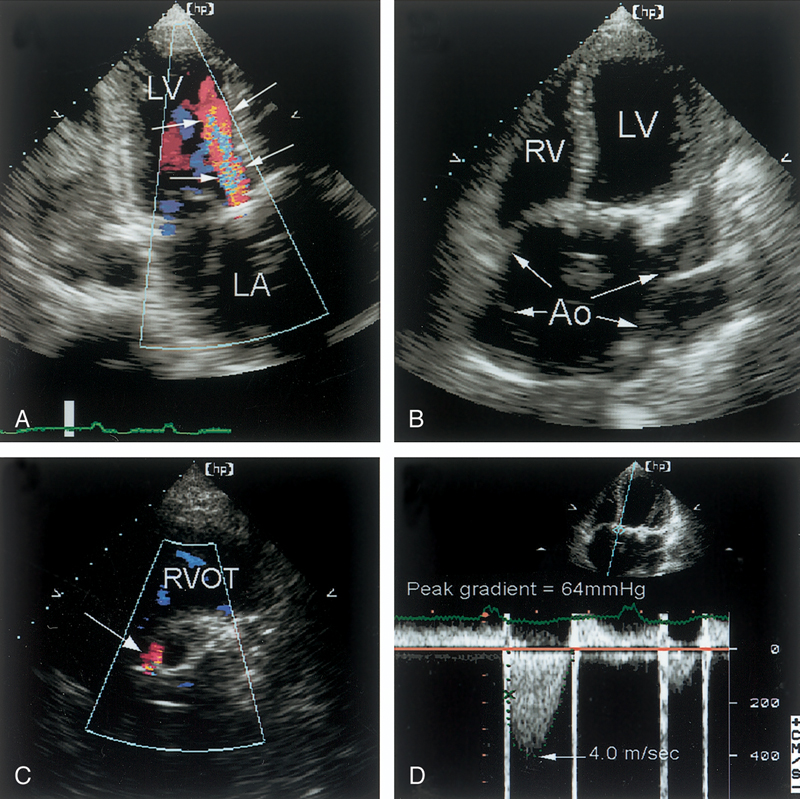

فحوصات تشخيصية لبعض امراض القلب والشرايين التاجية